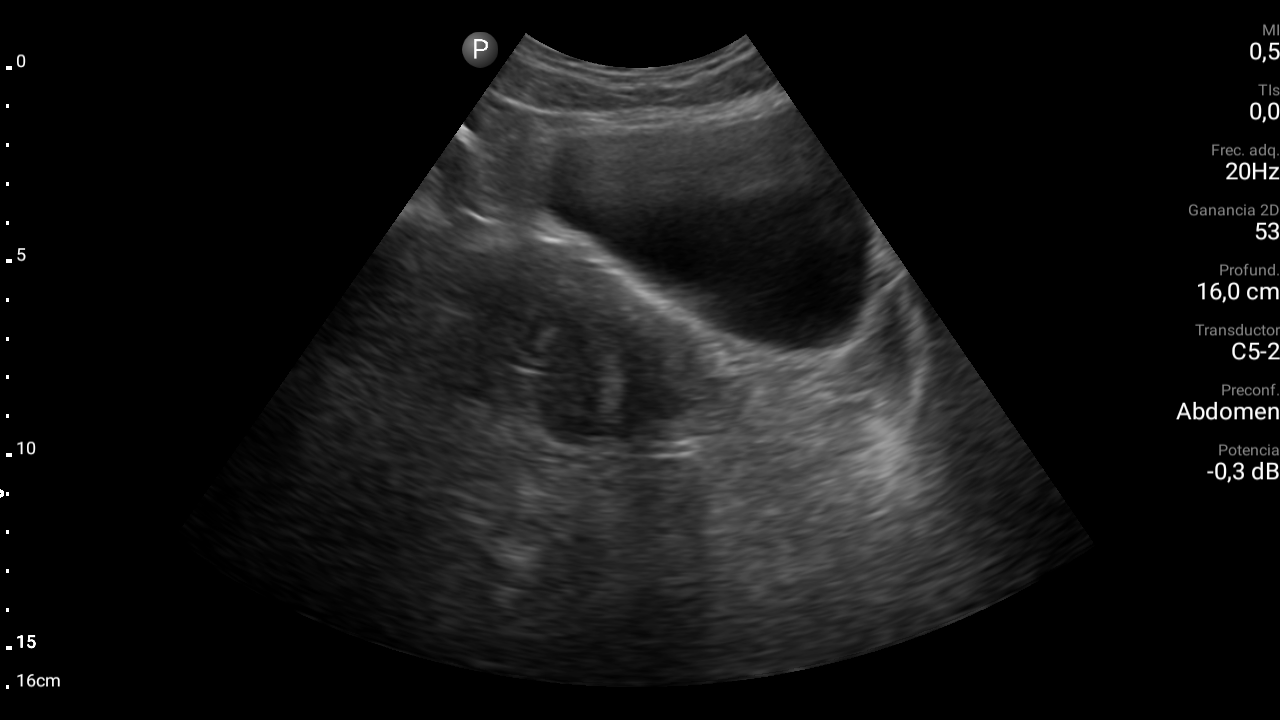

En ecografía abdominal se observa masa hipoecoica dependiente de útero por lo que se remite de forma preferente a ginecología.

En ginecología le realizan ecografía transvaginal, siendo diagnosticada de mioma uterino.